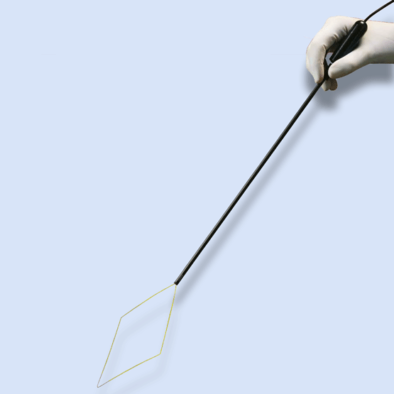

LiNA Bipolar Loop™

Laparoscopic Supracervical Hysterectomy (LSH) & subserosal pedunculated myomectomy

The LiNA Bipolar Loop facilitates the same outstanding features as the LiNA Gold Loop, which reformed the market for Laparoscopic Supracervical Hysterectomy (LSH). This next generation loop uses bipolar energy to section the uterus in few seconds – reducing both procedure time and number of traditional cutting and coagulation instruments.The LiNA Bipolar Loop is additionally designed to simplify subserosal pedunculated myomectomy, resectioning the myoma in one clean cut.

Low energy high effect

The LiNA Bipolar Loop underlines the importance of safety during every procedure

Optimum efficiency

The bipolar energy enables an instant cut with optimum efficiency at a low effect, using only 55-70 watts.

The fact that no neutral plate is needed improves the safety of the patient

Protective ceramic tip

A protective ceramic tip substantiates the safety by contracting the cutting area to only including the sides of the loop.

In addition the ceramic tip ensures correct retraction of the loop.

Improved visualization

The coloured insulation of the electrode provides a comprehensive view for positioning and improving the visualization on the monitor.

The ceramic tip amplifies the correct placement of the loop around the cervix due to easy identification of the electrode.

One clean cut in few seconds!

The functional design strengthens the intuitive and easy-to-use ability of the LiNA Bipolar Loop.

• Ready and easy to operate

When the handle is pushed forward the cutting loop opens instantly and is ready for immediate positioning around the uterus or myoma.Placement of hands is indicated by a rugged surface on both handle and tube thereby ensuring optimal manoeuvring.

• Cut and coagulation in one simple step

In one simple move the retraction of the loop ensures both cut and coagulation leaving a nice clean surface. This technique minimizes the need for post-coagulation of the cervix or peduncle.

• Ergonomic surgical position

By eliminating traditional coagulation and cutting devices the surgical time is reduced with several minutes and in addition the loop induces a more ergonomic working environment due to the shortened procedural time.

Applicable for various sizes of uteri and myomas

The versatility of the LiNA Bipolar Loop emphasizes the adaptation to the various sizes of uteri or myomas.

- 3 loop sizes: standard (160mm x 80mm), large (200mm x 100mm) and x-large (240mm x 120mm)

- It is supplied with a fixed 2-pin 4mm male bipolar plug (with 29mm distance) or EURO connector